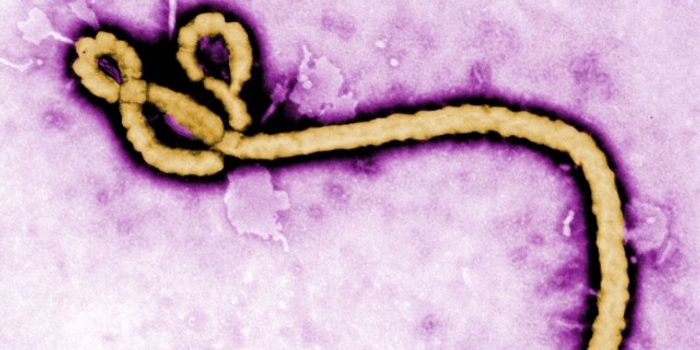

OCT 05, 2021ImmunologyMany of the deadly viruses that affect humans—including Ebola and HIV—have animal origins. These infectious ...

JUL 19, 2017MicrobiologyAs if getting Ebola isn’t bad enough, some survivors continue to harbor the virus in their eyes. Researchers at Fl ...